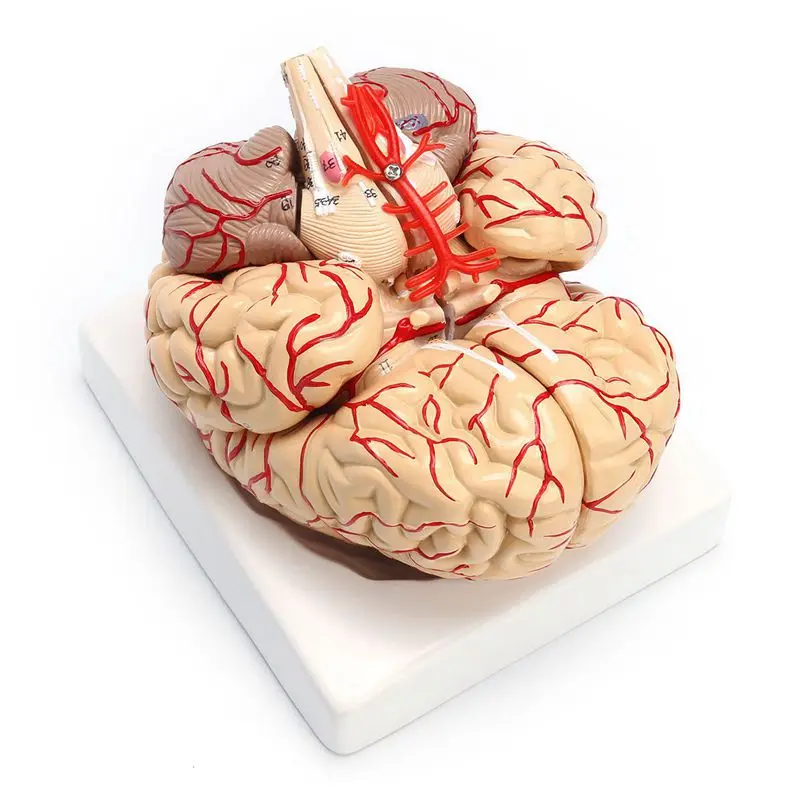

1: 1 Life Size Human Anatomical Brain Pro Dissection Medical Organ Teaching Model

sku: 4000775317276

ACCORDING TO OUR RECORDS THIS PRODUCT IS NOT AVAILABLE NOW

$29.20

Shipping from: China